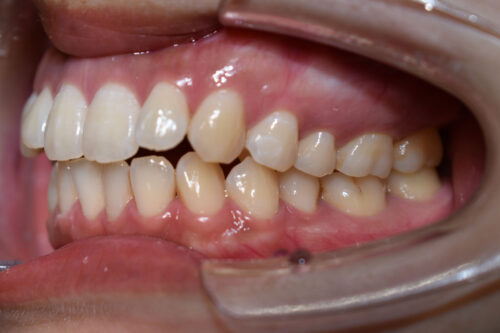

初診時年齢28歳女性

歯のがたつき(叢生)と

出っ歯

顔の長さを気になさり

巣鴨 ・ 池袋よりひとつ隣駅の東京都豊島区大塚駅すぐの大塚たまみ矯正歯科へ

来院されました。

かみ合わせは

奥歯が出っ歯方向へ

また 下方へ成長し ずれた状態で

開咬を呈しておりました。